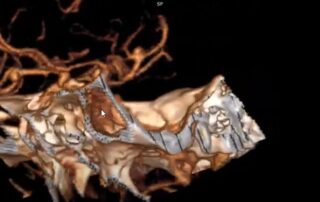

Леонтьєв Олексій2026-01-05T18:54:24+02:00У цьому відео ми демонструємо сучасний малоінвазивний підхід до лікування стенозу поперекового відділу хребтового каналу на рівні L2–L3 у пацієнтки 75 років. Операція виконана методом унілатеральної біпортальної ендоскопії [...]